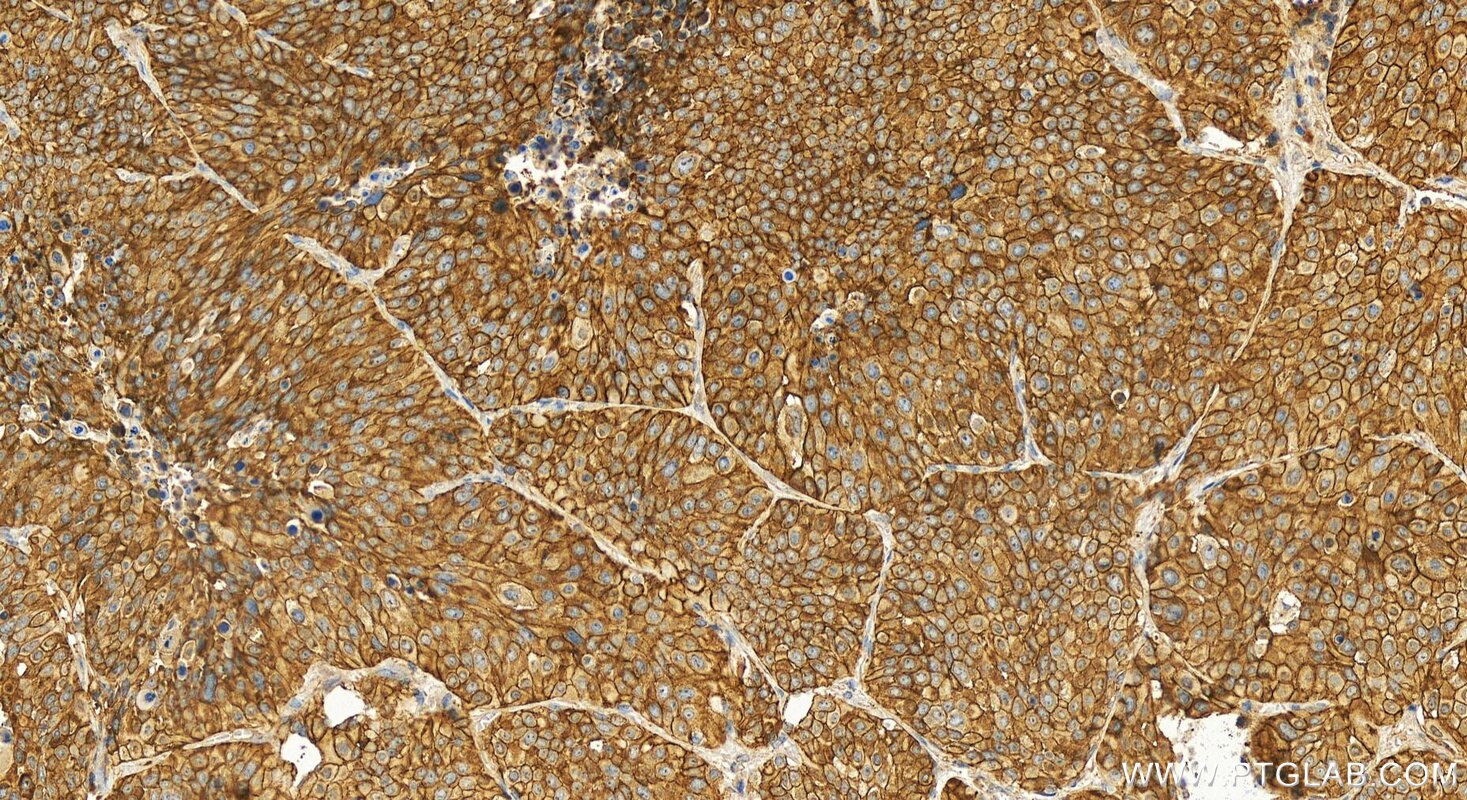

| Positive IHC detected in | human lung squamous cell carcinoma tissue Note: suggested antigen retrieval with TE buffer pH 9.0; (*) Alternatively, antigen retrieval may be performed with citrate buffer pH 6.0 |

31198-1-AP targets KIAA1522 in IHC, ELISA applications and shows reactivity with human samples.